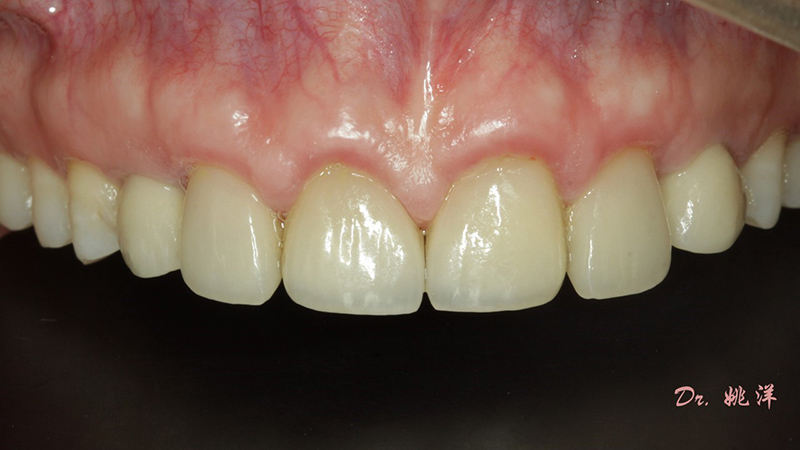

從最終修復(fù)效果可以看出:23,24間隙不足修復(fù)兩顆,修復(fù)為1顆牙。因為經(jīng)過數(shù)字化設(shè)計和精確導(dǎo)航植入,修復(fù)體齦緣協(xié)調(diào)自然

術(shù)后照片

恢復(fù)了正常的淺覆合淺覆蓋